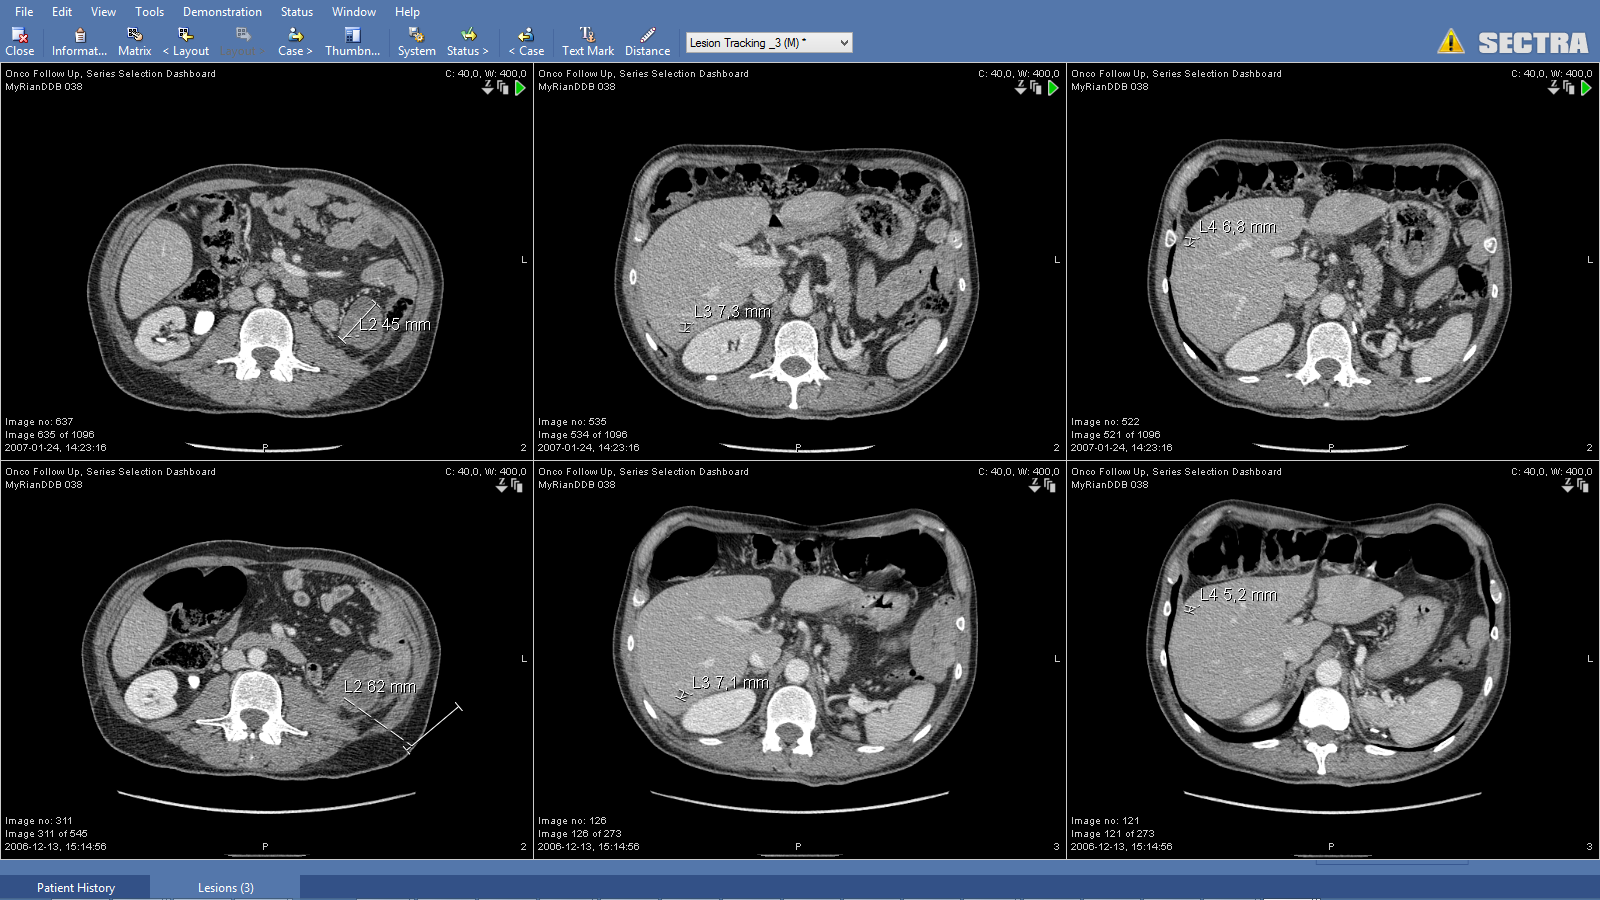

Screenshot from Sectra Lesion Tracking application

SLT is a tool that is integrated into the diagnostic application of the Sectra Enterprise Imaging Solution. It provides functionality for tagging and measuring lesions, a snapshot presentation and an overview of the measured and tagged lesions.

For follow-up studies, the Sectra Anatomical Linking functionality works in symbiosis with SLT and recognizes similar anatomical positions, which facilitates and significantly increases the accuracy of the lesion comparison procedure.

Together, these functionalities provide a snapshot presentation, a quick overview of lesions, and more efficient measurements and follow-up calculations without having to scroll through the exam.

The SLT tool was determined to be more efficient the more prior exams the patient had. The time saved was also determined to be greater for patients with more than one lesion. This is because SLT creates a library of lesion snapshots to give an easy overview, as shown in image 1. Note that all cases were assessed to be complex cancer cases.

Image 1. A screenshot of the Sectra Lesion Tracking tool showing measurements of four lesions at two different timepoints.